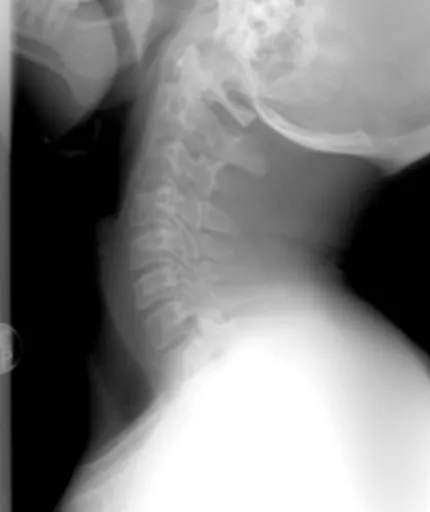

2.1. 허리 디스크 (추간판 탈출증)

가장 대표적인 신경 압박 원인 중 하나가 바로 허리 디스크, 즉 추간판 탈출증이에요. 허리 척추뼈 사이의 디스크(추간판)가 제자리에서 밀려나와 주변 신경을 누르는 거죠. ** 이때 신경이 눌리는 위치에 따라 엉덩이부터 다리까지 뻗치는 통증이나 저림, 감각 이상이 나타날 수 있어요. ** 허리도 아프고 다리도 저리다면, 의심해 볼 만해요.

2.2. 좌골신경통

좌골신경은 우리 몸에서 가장 굵고 긴 신경 중 하나인데, 허리에서 시작해서 엉덩이를 지나 다리 뒤쪽으로 내려가요. 이 좌골신경이 어떤 이유로든 압박받거나 자극받으면 좌골신경통이 발생하는데, 이때 엉덩이에서 시작해 다리까지 찌릿찌릿하거나 타는 듯한 저림 증상이 나타날 수 있답니다. 오래 앉아 있거나, 허리에 무리가 가는 활동을 할 때 더 심해지기도 해요.